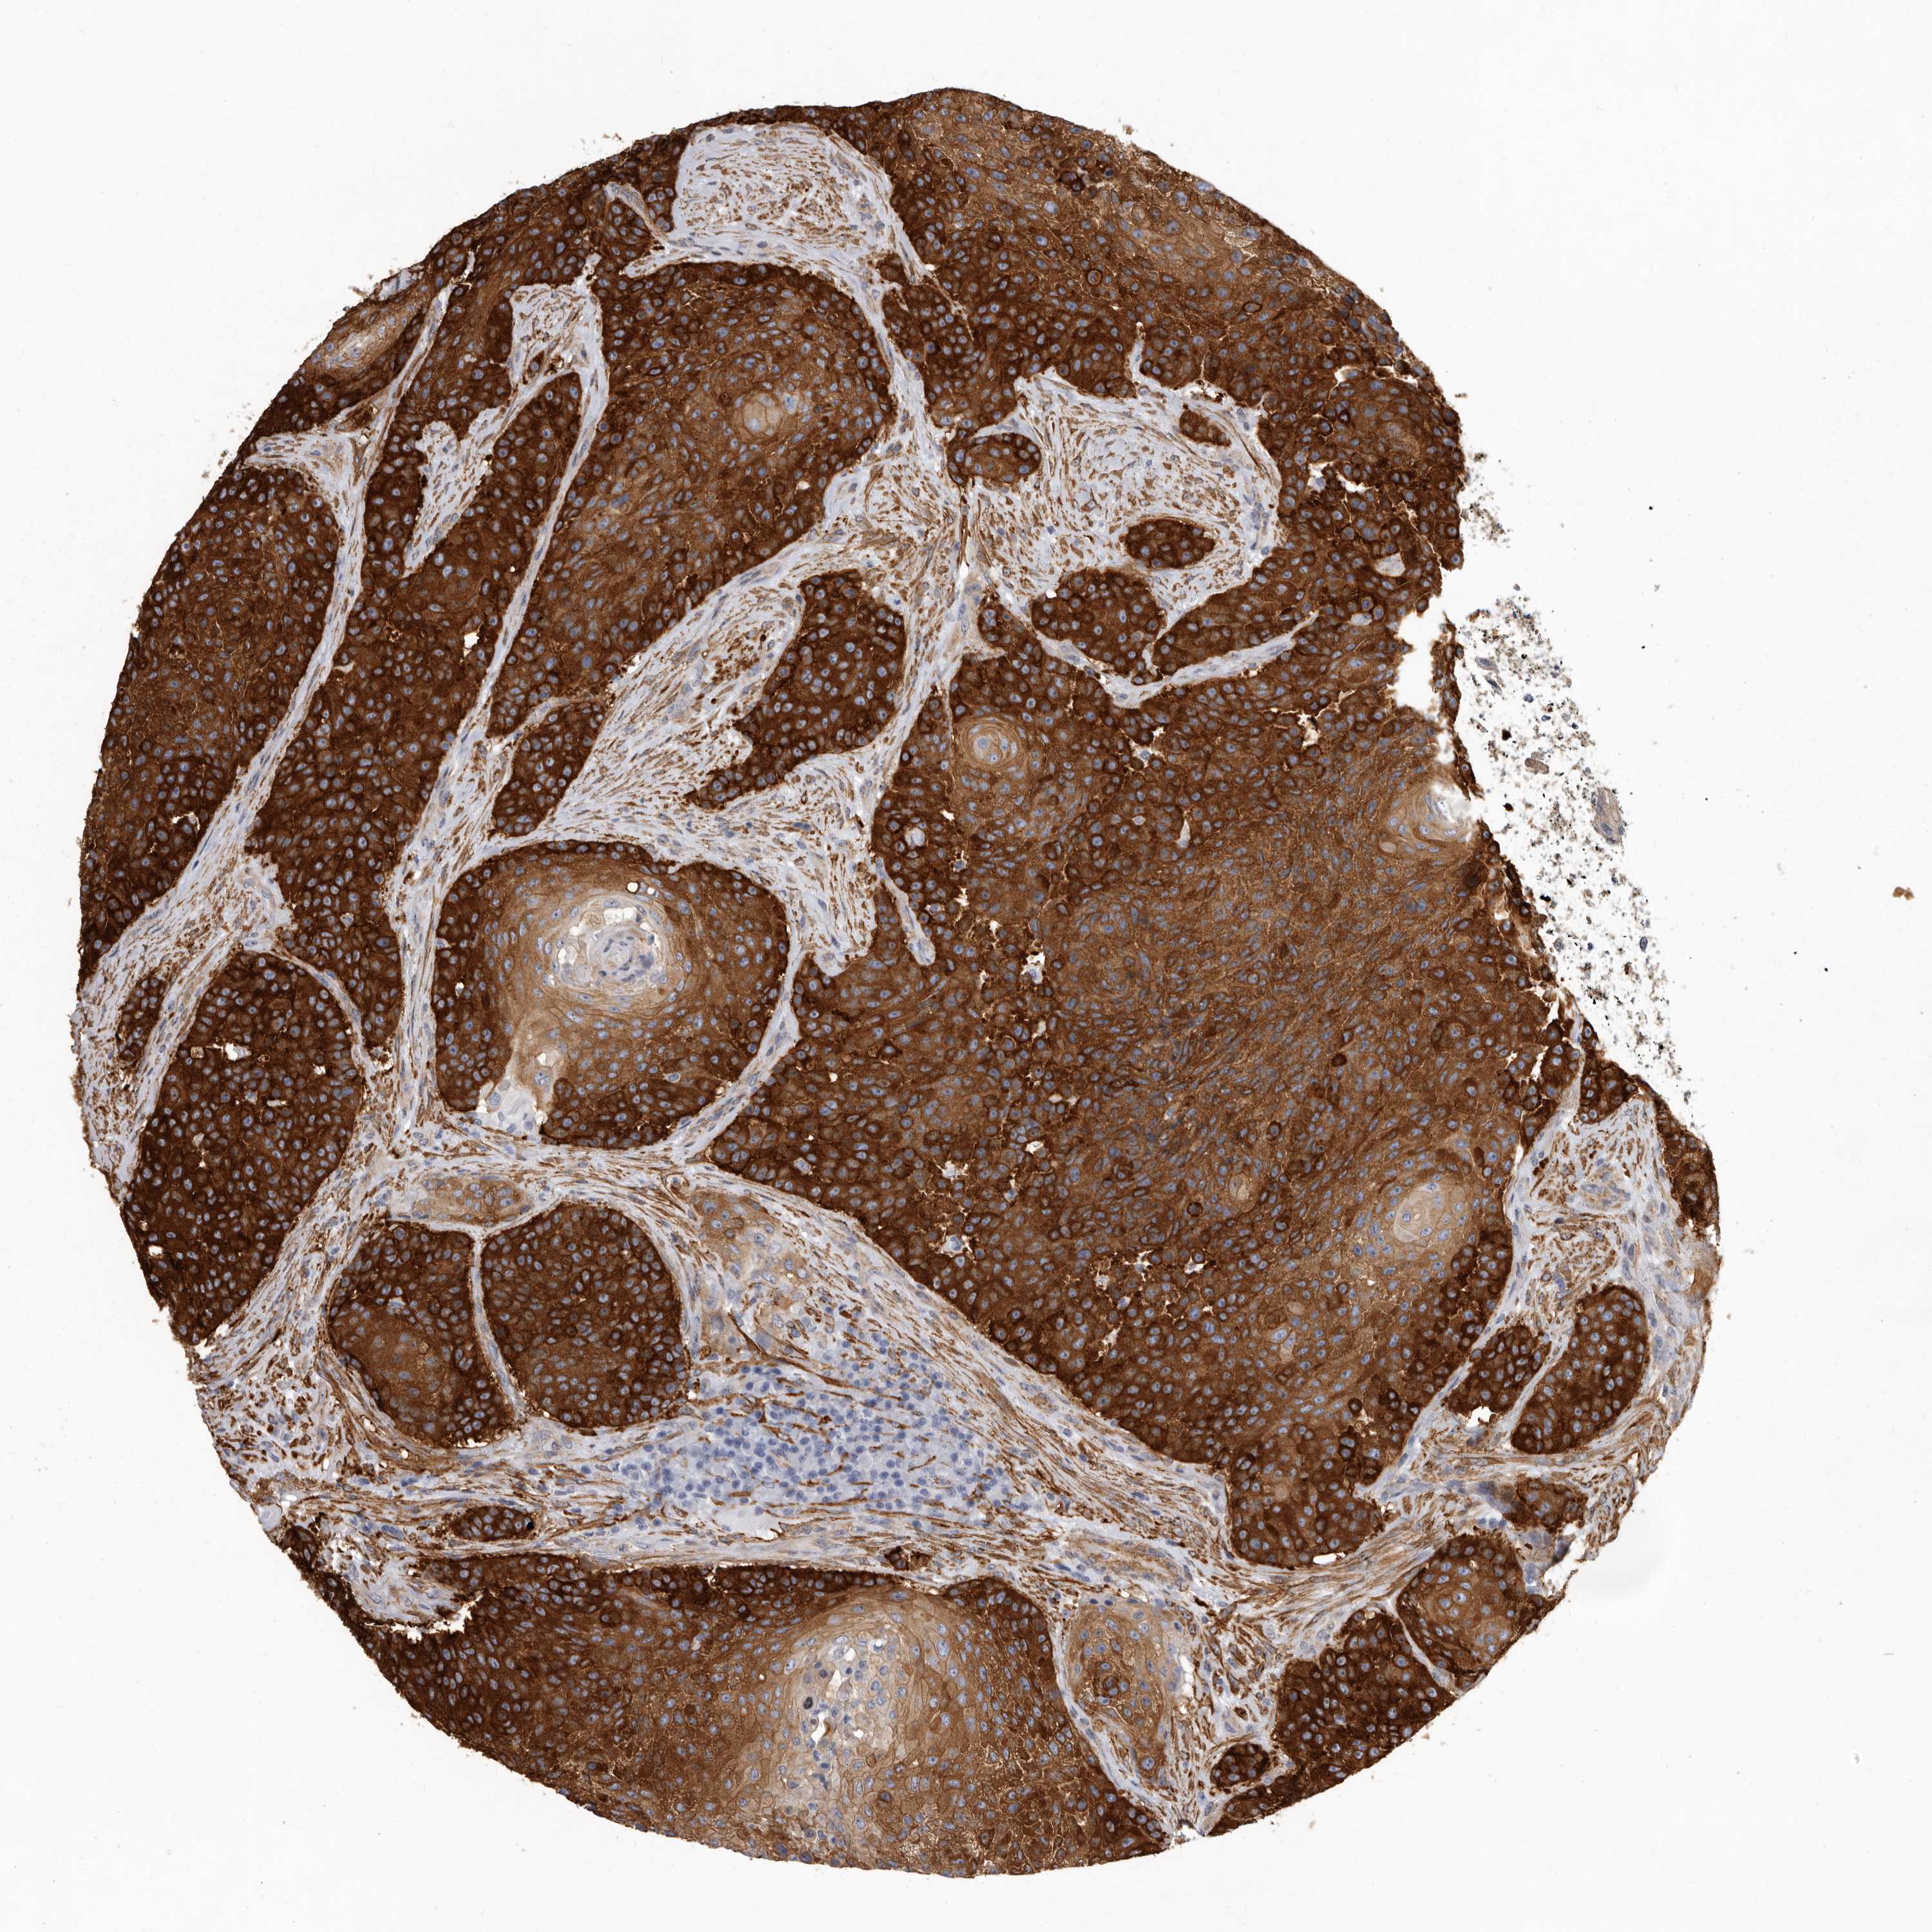

UROTHELIAL CANCER - Protein expressioni

A mouse-over function shows sample information and annotation data. Click on an image to view it in a full screen mode. Samples can be filtered based on level of antibody staining by selecting one or several of the following categories: high, medium, low and not detected. The assay and annotation is described here.

Note that samples used for immunohistochemistry by the Human Protein Atlas do not correspond to samples in the TCGA dataset.

Antibody stainingi

Antibody staining in the annotated cell types in the current human tissue is reported as not detected, low, medium, or high, based on conventional immunohistochemistry profiling in selected tissues. This score is based on the combination of the staining intensity and fraction of stained cells.

Each image is clickable and will lead to virtual microscopy that enables deeper exploration of all samples and also displays staining intensity scores, fraction scores and subcellular localization as well as patient and tissue information for each sample.

Antibody HPA028448

Antibody HPA028696

Urothelial carcinoma, Low grade

Urothelial carcinoma, High grade